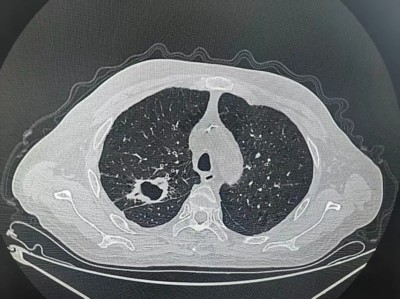

张大叔第一疗程治疗前后对比

治疗前

治疗第一个疗程后

2026年1月下旬,第一疗程顺利结束,复查影像显示:肿瘤较治疗前明显缩小,咳嗽频率减少,未出现咯血症状。